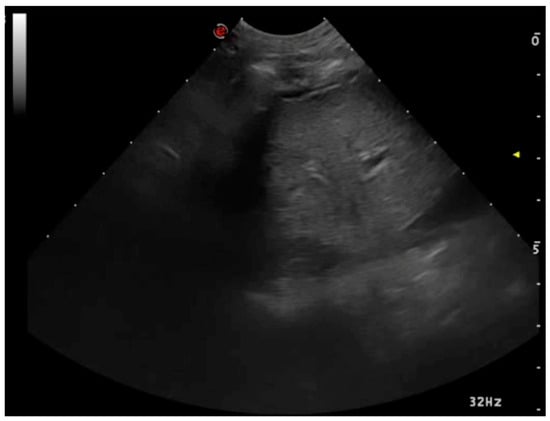

3.1.2. Pleural Effusion